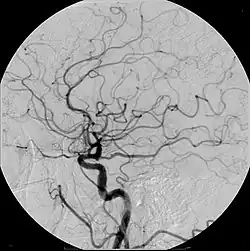

Digitale Subtraktionsangiographie

Die digitale Subtraktionsangiographie (DSA) ist eine Methode zur separaten Abbildung von Blutgefäßen mittels Röntgenstrahlung.[1] Es handelt sich um eine Form der Angiographie, dient also der Untersuchung von Blutgefäßen. Ihr Vorteil gegenüber der sogenannten konventionellen Blattfilmangiographie liegt darin, dass „störende“ Bildaspekte durch die Subtraktion unsichtbar sind. Die DSA ist ein Verfahren der Projektionsradiographie, das mit Magnetresonanzangiographie, Computertomographieangiographie und Sonographie konkurriert.[2][3]

Hierbei werden vom zu untersuchenden Körperteil, zum Beispiel dem Mediastinum,[4] dem Unterbauch[5] oder dem Gehirn, mehrere zeitlich aufeinander folgende Bilder erstellt. Während der Aufnahmesequenz wird ein Kontrastmittel in Blutgefäße gespritzt. Es resultieren eine Aufnahme ohne Kontrastmittel, auch als Maske bezeichnet, und weitere Aufnahmen mit Kontrastmittelverteilung. Das digitale Maskenbild wird von den nachfolgenden Bildern subtrahiert. Übrig bleiben nur die Teile des Bildes, die sich unterscheiden, also genau die (durchbluteten) Blutgefäße. Durch die Erstellung mehrerer Bilder zu verschiedenen Zeitpunkten, die auf ein Maskenbild folgen, können filmähnliche Bildsequenzen erstellt werden. Ebenso ist eine farbkodierte Darstellung möglich, indem die Grauwertkurven für die Bildpixel auf Farbwerte abgebildet werden.